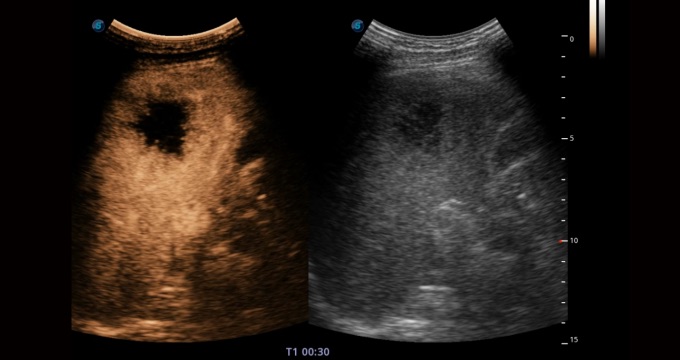

• Imágenes de contraste

Los agentes de contraste proporcionan una fuerte reflexión de la señal, dando una imagen mejorada del flujo sanguíneo difícil de ver. Controla la presión acústica y proporciona una calidad de imagen prometedora con una dosis de agente más pequeña.